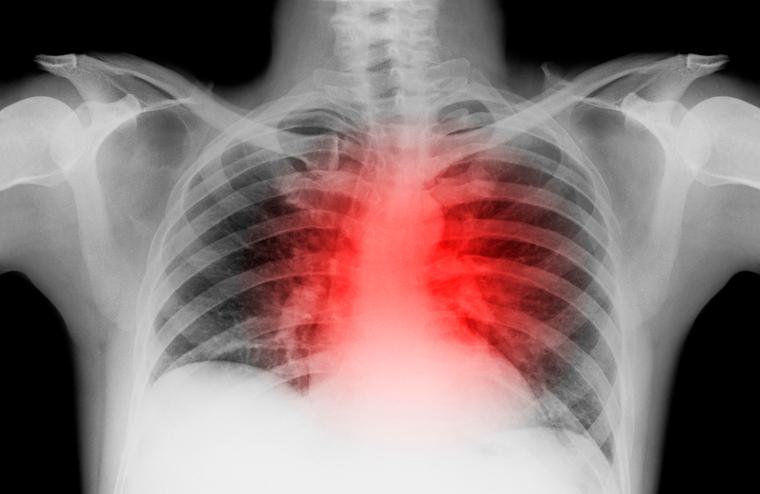

In heart failure, the organ loses the ability to pump adequate blood for the body's needs. This can lead to fatigue, wheezing, weakness, swollen legs and feet and, ultimately, death.

Heart failure is a progressive condition – meaning it grows worse with time – in which the heart loses the ability to pump blood. This can lead to fatigue, wheezing, weakness, swollen legs and feet and, ultimately, death.